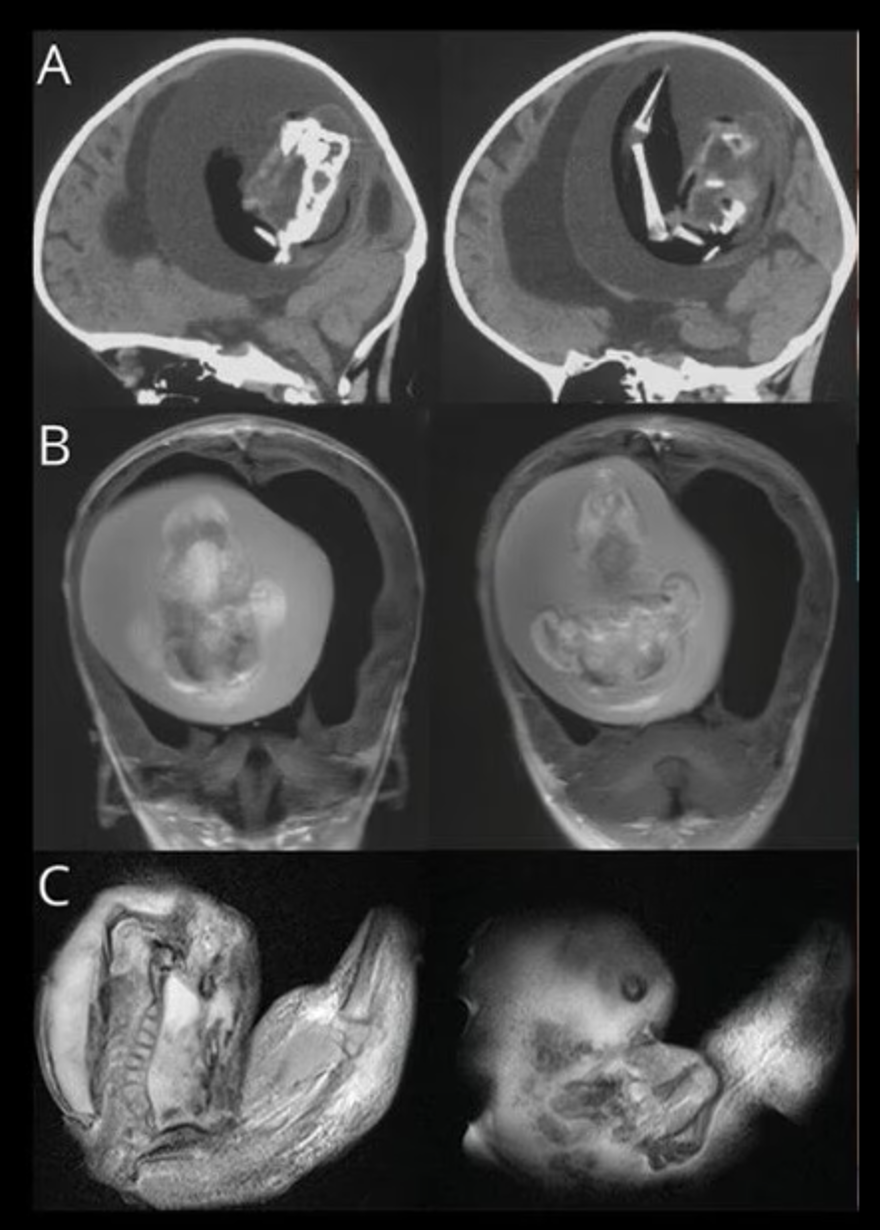

Çin'de doğmamış ikizinin fetüsü, bir yaşındaki kız bebeğin kafatasından ameliyatla çıkarıldı. 'Fetüs içinde fetüs' adı verilen oldukça nadir vakada, doktorlar fetüsün üst uzuvlarının, kemiklerinin ve hatta tırnaklarının gelişmiş olduğunu, yani kardeşinin içindeyken aylarca büyümeye devam ettiğini söyledi.Yaklaşık beş santim uzunluğundaki fetüs, ancak ebeveynler kızlarını kafası büyüdüğü ve motor becerilerinde sorunlar yaşadığı zaman doktora götürdüklerinde fark edildi.

Şangay'daki doktorlar, doğmamış ikizin fetüsünün çocuğun beyninde geliştiğini tespit etti. Çalışmanın yazarları, "Motor becerilerinde gecikmesi ve genişlemiş baş çevresi olan 1 yaşındaki bir kız çocuğunda malforme olmuş monokoryonik diamniyotik ikiz olan intraventriküler fetüs içinde fetüs (fetus-in-fetu) tespit edildi." denildi.